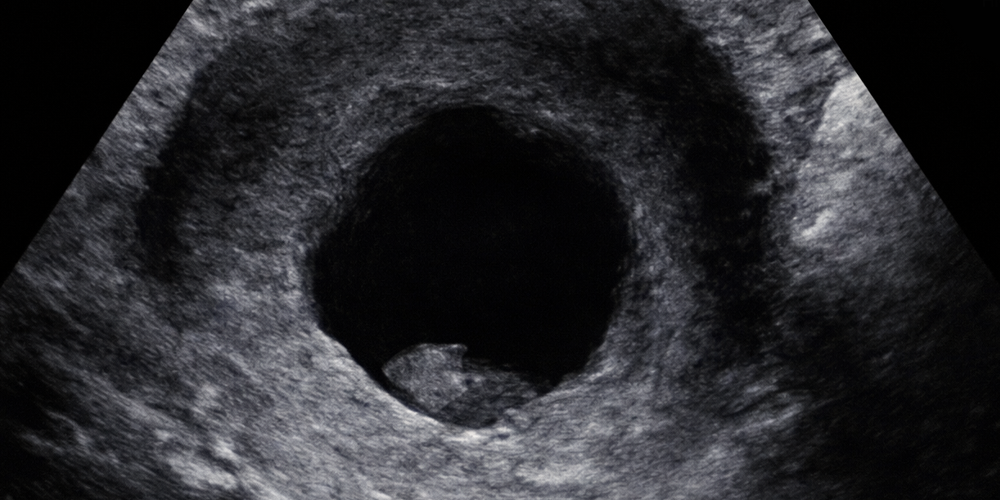

Kalp anomalileri en sık görülen doğumsal anomaliler listesinin başında yer almaktadırlar. Bu grubun sayısını çoğaltan septal defektlerin (kalpteki ara duvar delikleri) çoğu küçük ve önceden bilinmesinin önemli olmadığı durumlardır. Ve büyük çoğunluğu bebeğin akıbetini etkilemeyecek hastalıklardır. Yani, doğumdan sonra kalpte üfürüm olarak bulgu verdiği için yakalanan, üçer ay aralarla izlenip yüzde doksanının bir yaşına gelmeden düzeldiği durumlar. Bu grubun bu durumu bilmeleri ve bu kaygıları yaşamalarının karşılığı olarak kayda değer bir edinim var mı? Ben bilemiyorum. Kalbinde böyle küçük delik olduğunu görüp söylemek zorunda kaldığım bir çok ailenin bu senaryoyu yaşayıp, önce çocuklarının kalp hastası olduğu çöküntü ve üzüntüsünü yaşamalarını, ardından korku içinde kontrollerine gittiklerini, sonrasında da geçti düzeldi aşamasında oh diyebildiklerini izledim. "Hiç görmesek, hiç söylemesek mi?" dediğim de olmadı değil...

Ağır kalp sorunlarına gelince neyse ki onlar da çok seyrek.

Büyük kalp delikleri, ana damarlarda terslik veya ağır darlıklara bağlı olarak kalbin bir tarafının gelişememesi (hipoplastik sol veya hipoplastik sağ kalp sendromları), gibi...

Bu tür hastalıkların bazılarında yapılabilecek bir şey olmaması üzücü gerçek, ama bazılarında doğar doğmaz ameliyat veya seri ameliyatlar bir umut gibi görünüyor. Maalesef, bu uzun ve yorucu ameliyatların sonucunda elde edilebilen sonuçlar her zaman pek parlak olmuyor. Örneğin bir seri kalp ameliyatından sonra (dünyanın sadece bazı ülkelerinde ve oldukça pahalı tedaviler sonunda) en çok 10 yaşına kadar yaşatılabilen bir çocuk tedavi edilmiş oluyor mu? Üstelik çoğunluğu zihinsel engelli olan bu çocukların zihinsel engellerinin zaten baştan beri var olan hastalıklarının bir parçası mı, yoksa tekrarlayan ağır kalp ameliyatlarının bir sonucu mu olduğunu bilim cevaplayamıyorsa? Yine de tedavi yapmış oluyor muyuz? Ağır sorular, cevapları da oldukça ağır herhalde...

Yukarıdaki resimdeki kalbin yaşama şansının sıfır olduğu baştan belli. Kalbin sol tarafındaki karıncık hiç gelişememiş. Bu durumu anne karnında iken görebilmenin tek faydası aylar öncesinden kendilerini bekleyen acıyı aileye haber verebilmiş olmak... Bu durumda gebeliği erkenden düşükle sonlandırmak bir çözüm mü? Kişiye göre herkesin doğrusu değişir. Bana göre evet... Yapılabileceklerin en iyisi. Ama, anne-baba olarak gebeliği sonlandırma kararının sorumluluğunu ağır bulan, kabul etmeyen ve önceden belli acıları kabul edip yaşayanları da saygı ile karşılıyorum. Anne-baba olmanın ruh hali... Ben de babayım... Karışık iş...